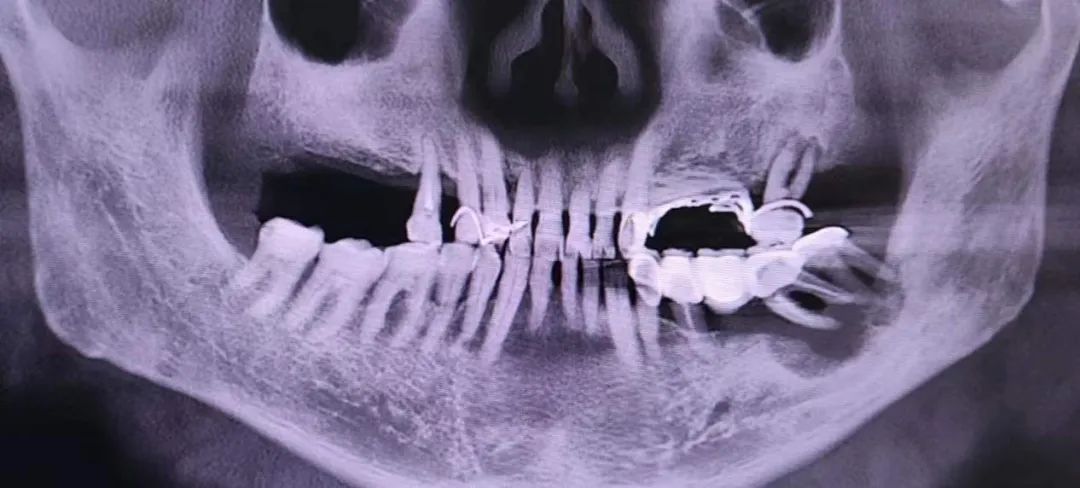

肿瘤导致下颌骨骨折破坏

切除口底、牙龈肿瘤及累计的下颌骨,并清扫同侧颈淋巴结,切除的病灶及下颌骨以及重建板恢复下颌骨外形轮廓。